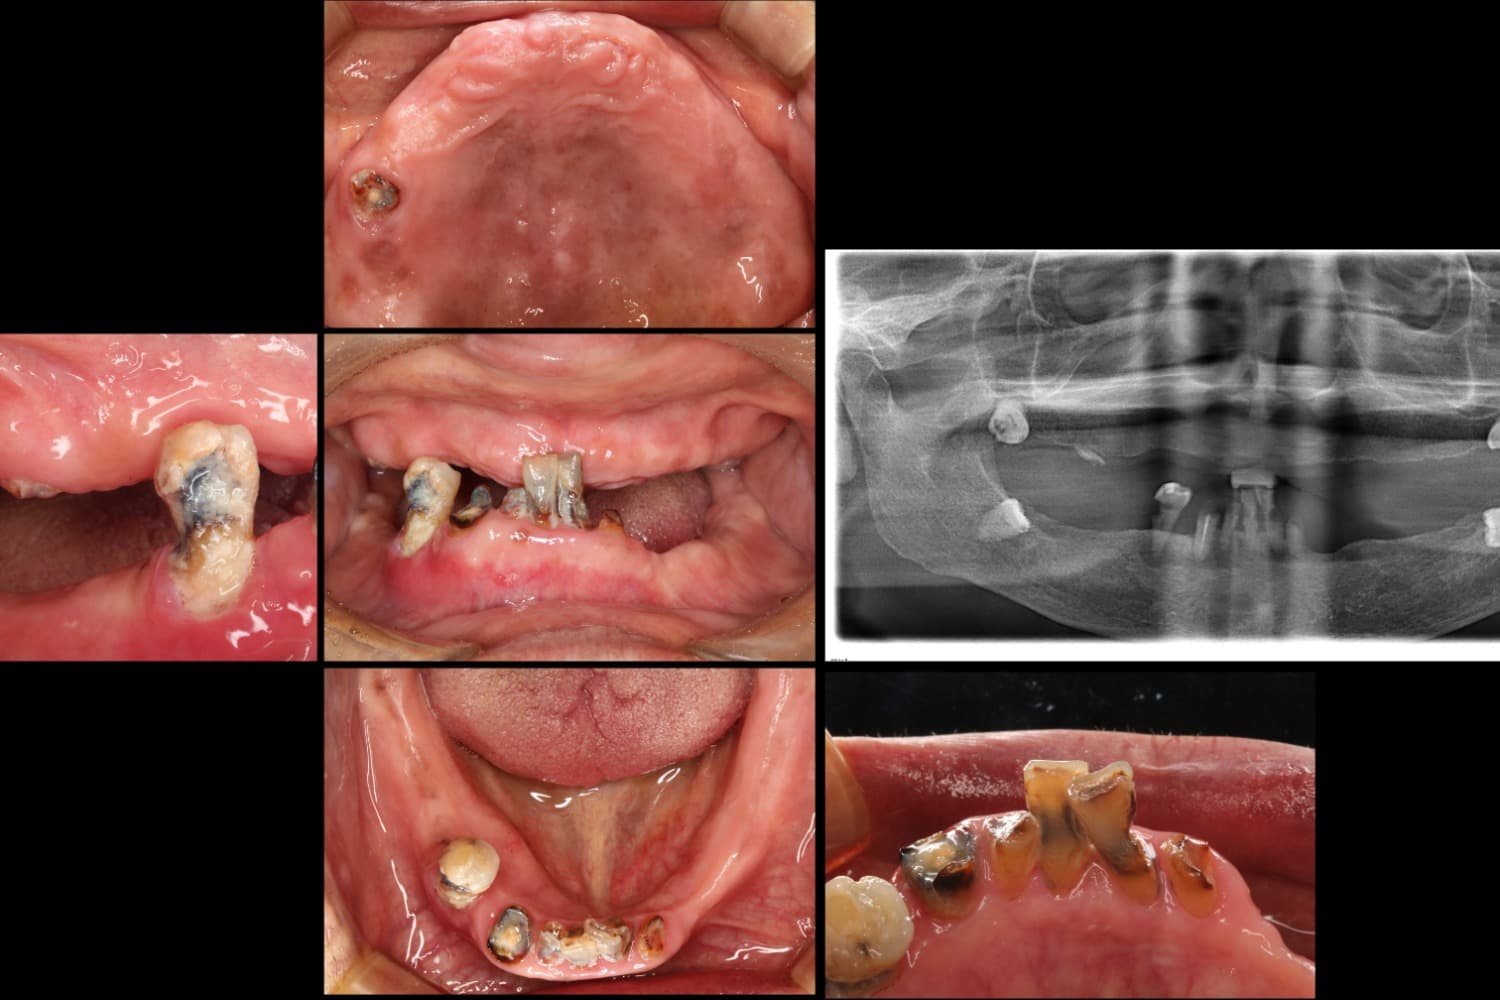

All-on-6による治療

Before

All-on-6という全部の歯をインプラントで補う治療 保存できる歯がない状態になっており、食事がまともにできないとのことでした。 インプラントを移植すると同時に被せ物も一緒に装着する方法で機能回復をおこないました。

年齢

70代

性別

男性

主訴

入れ歯が合わず、食事ができない

治療期間

5ヵ月

治療回数

10回

費用

CT 16,500円(税込) 静脈内鎮静法 66,000円(税込) ALL-ON-6 2,750,000円(税込)×2

副作用・リスク

歯周病に感染・発症し重度に進行するとインプラントが抜けてしまうことがあります。また、手術後は数日間腫れが出る場合があります。